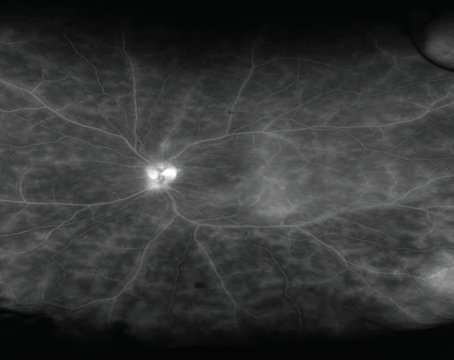

Imaging Forum

Morning Glory Syndrome

Imaging is key to correctly diagnosing this optic disc anomaly.